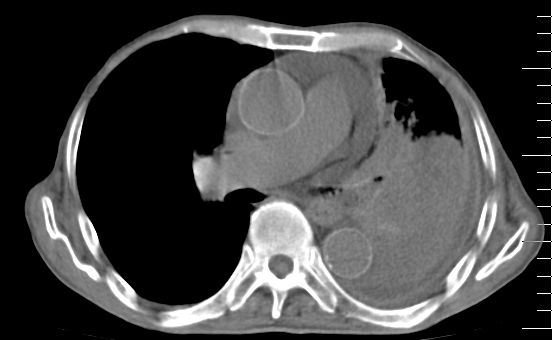

标题: CT10141:男、84岁,咳嗽、咯血1年。 [打印本页]

标题: CT10141:男、84岁,咳嗽、咯血1年。

支持左侧中央型肺癌伴下叶肺不张\\纵隔淋巴结转移.左侧包裹性胸腔积液\\心包积液.左侧少量胸腔积液..慢性支气管炎伴部分间质纤维化.

支持:左侧中央型肺癌伴下叶肺不张\\纵隔淋巴结转移.左侧包裹性胸腔积液\\心包积液.左侧少量胸腔积液..慢性支气管炎伴部分间质纤维化.另:支气管分支根部明显阻塞 狭窄,内膜凸凹不平,提示内膜增生物。

咯血病史较长,左肺下叶实变,体积未明显缩小,隐约可见血管影及坏死阴影,双肺门及纵隔淋巴结增大,心包增厚积液,纵隔右移位,单侧胸腔积液,首先考虑:大叶型肺泡癌伴纵隔心包转移。